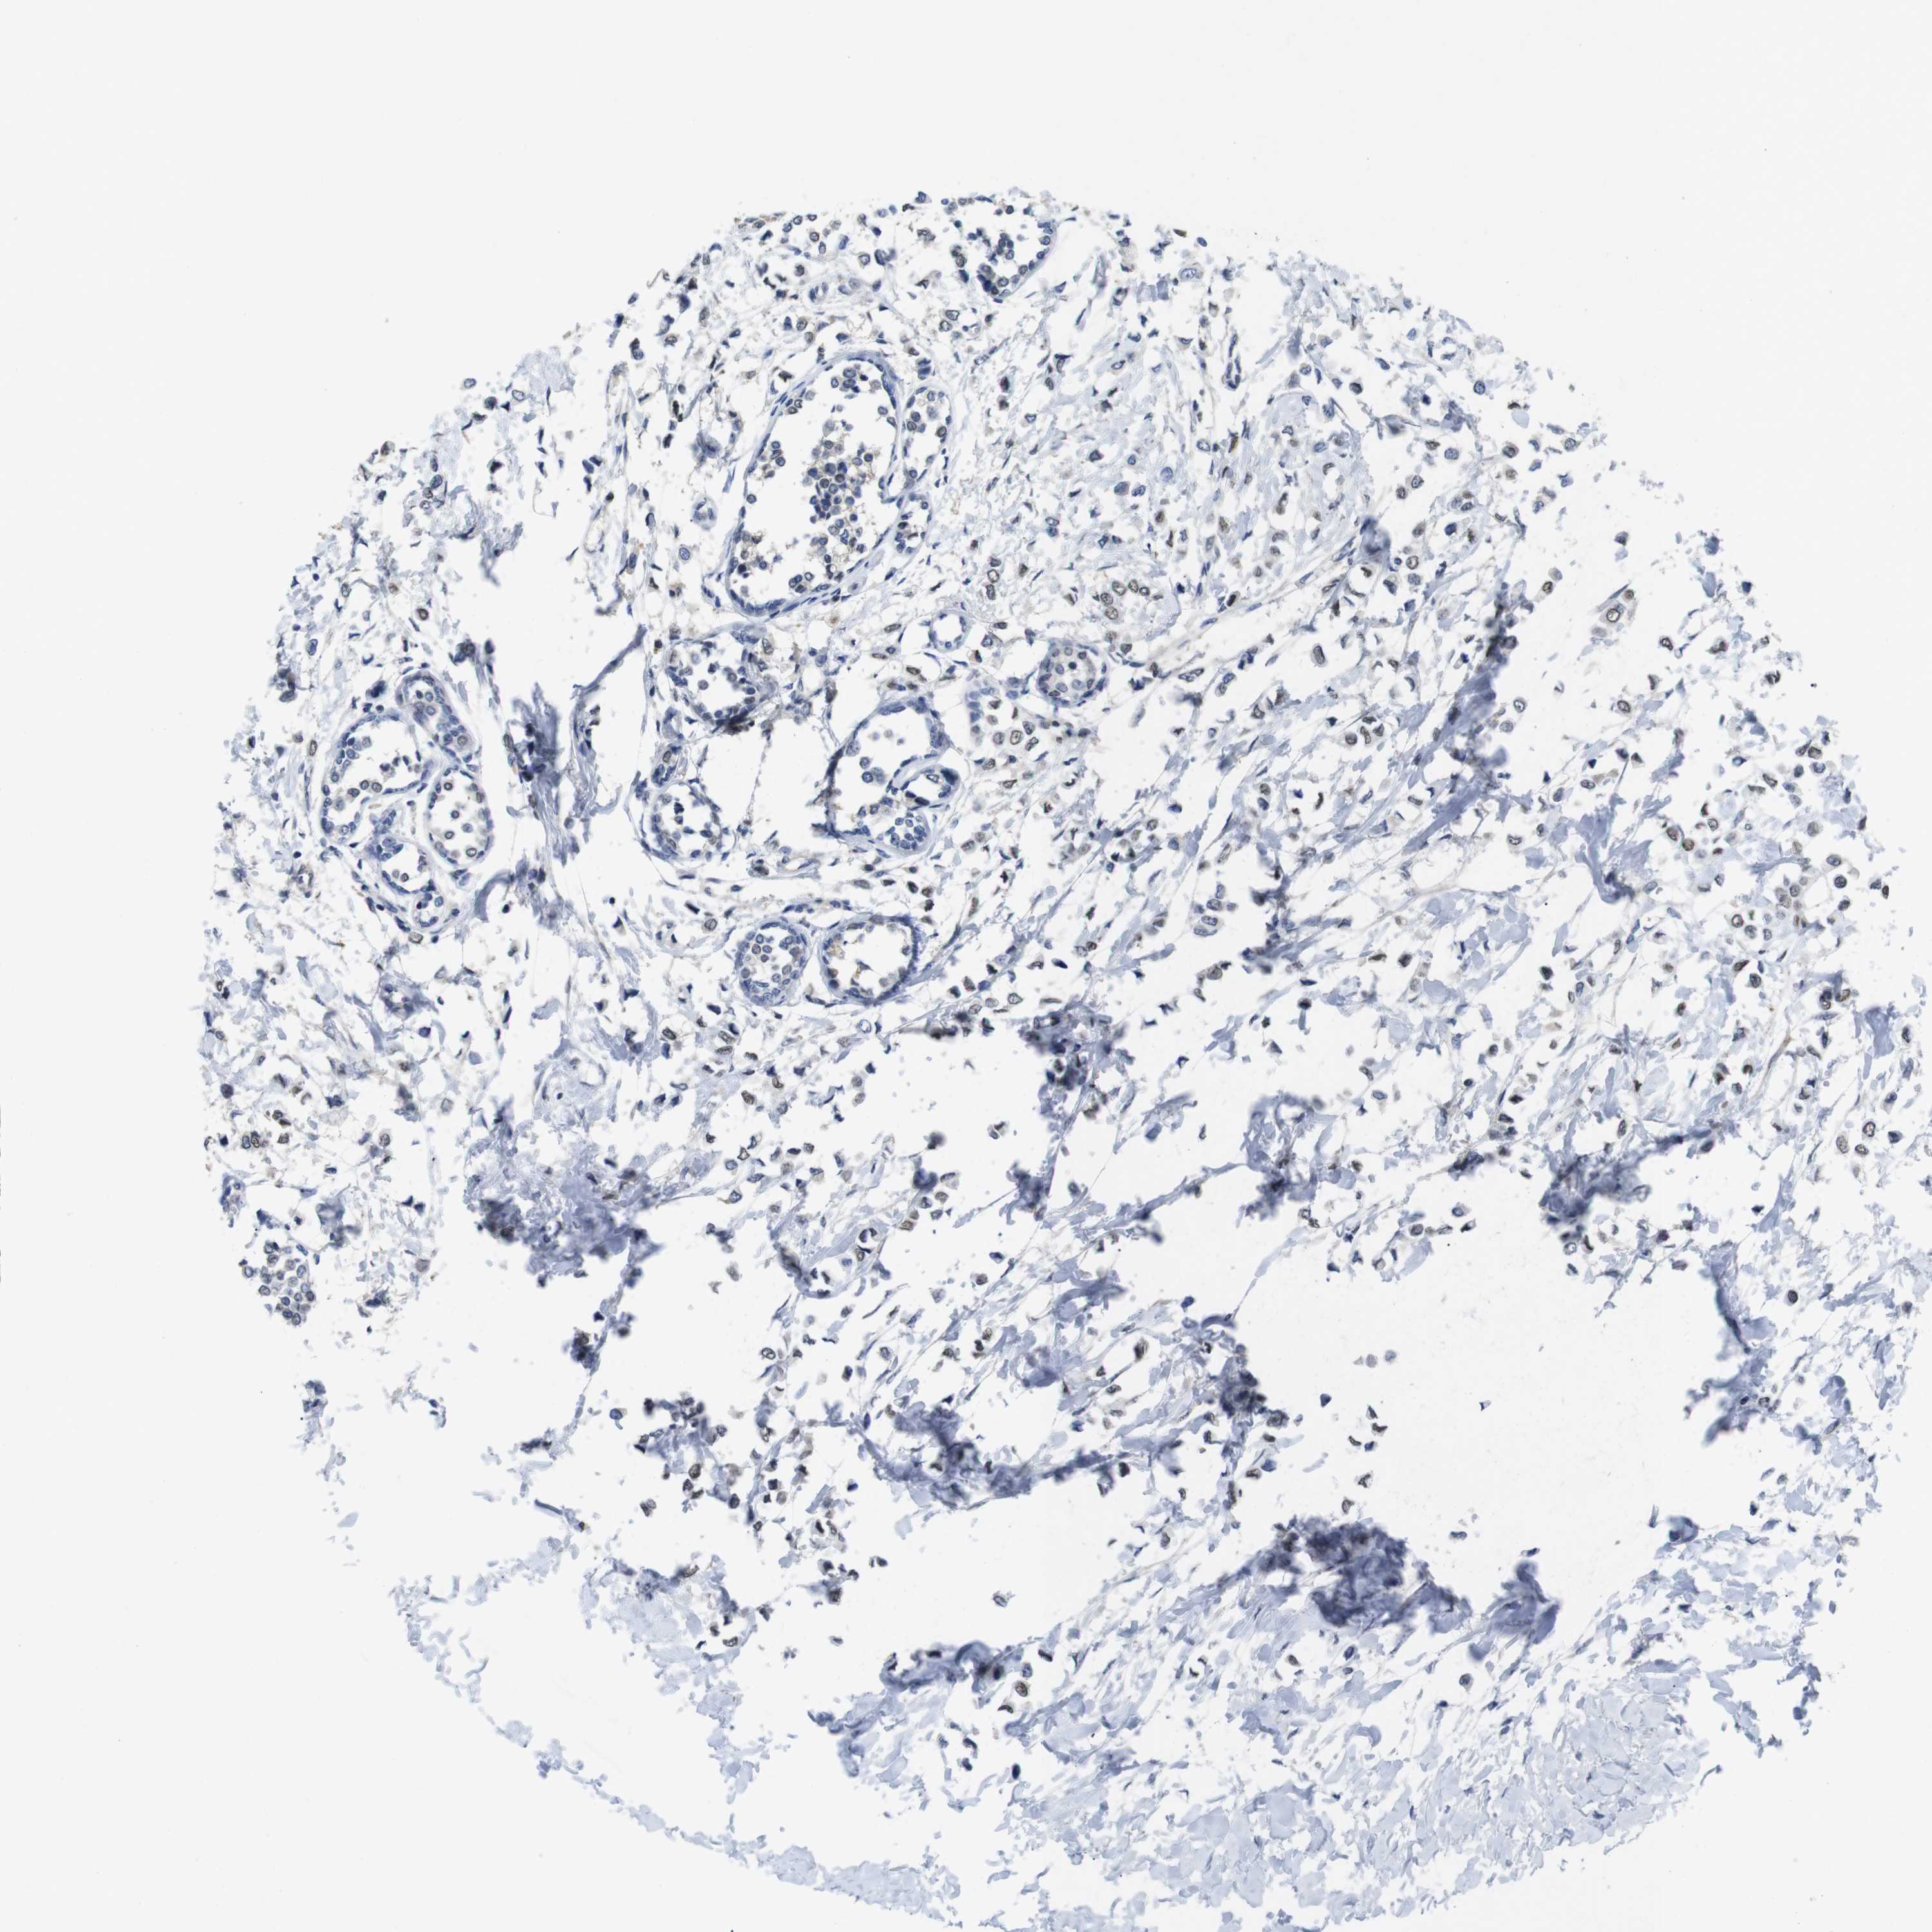

CANCER BREAST CANCER Show tissue menu

BRCA TCGA BRCA VALIDATION PROTEIN EXPRESSION